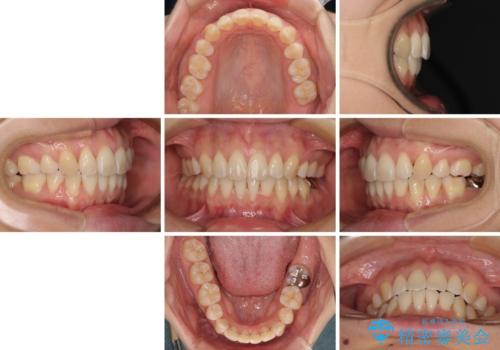

前歯のデコボコを抜歯矯正で改善 メタル装置で費用を抑える

もう少し口元の突出感を改善したかったのですが、舌の突出癖が影響し下顎前歯が唇側に押させる仕上がりとなりました。

- 矯正治療後の保定が不十分だと後戻り(元の位置に戻ろうとする動き)をします